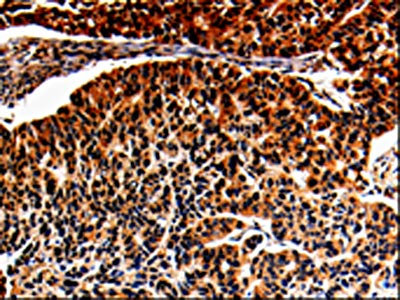

The image is immunohistochemistry of paraffin-embedded Human lung cancer tissue using CSB-PA787659(ALOX5 Antibody) at dilution 1/25. (Original magnification: ×200)

The image is immunohistochemistry of paraffin-embedded Human esophagus cancer tissue using CSB-PA787659(ALOX5 Antibody) at dilution 1/25. (Original magnification: ×200)